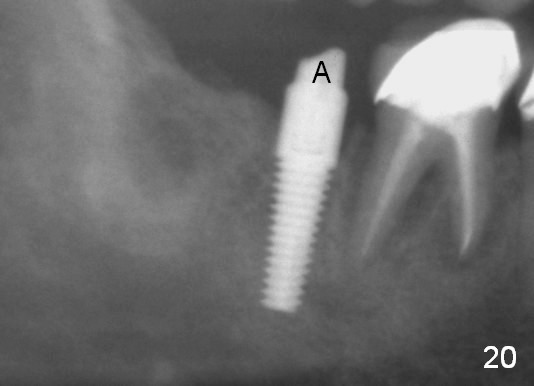

Four months postop, there is a sign of osteointegration (Fig.16 <). Graft particles migrate to the surface of the mucosa (Fig.17 <). A healing cuff is placed over the implant for preparation of restoration (Fig.18 H); graft particles are removed (<). Due to insurance issue, the restoration is yet to finish by 6 months postop (Fig.19 C: healing cuff); the cystic lesion appears to have been decreased concentrically (*). The bone density in the former cyst area continues to increase 14 and 32 months postop (Fig.20 A: abutment; Fig.22). Small piece of bone graft (<) is being extruded distobuccal to the #31 crown (C) asymptomatically 15 and 32 months postop (Fig.21,22).